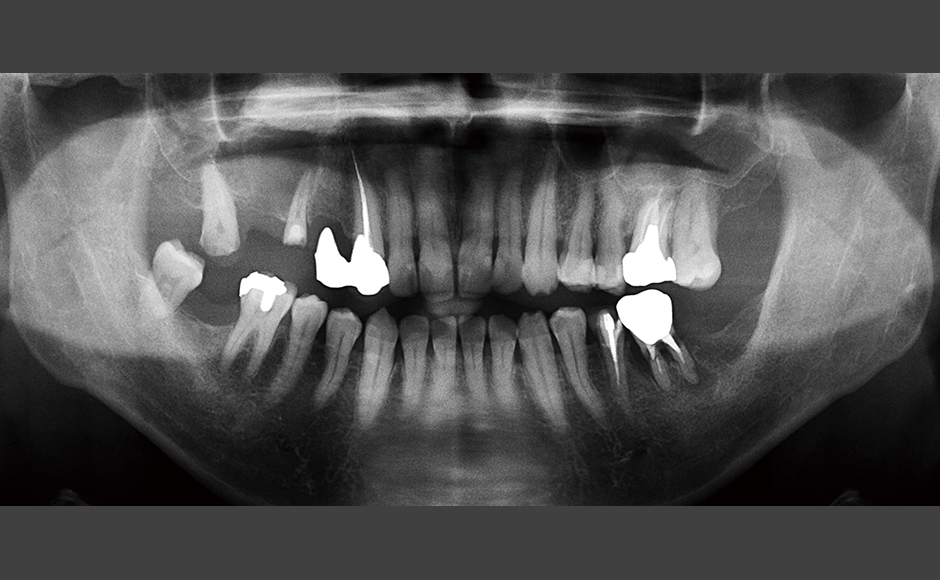

症例.1:穿孔を伴う根尖性歯周炎に対して非外科的歯内療法を行った症例

症例.2:外科的歯内療法を併用して根尖性歯周炎の治療を行った症例